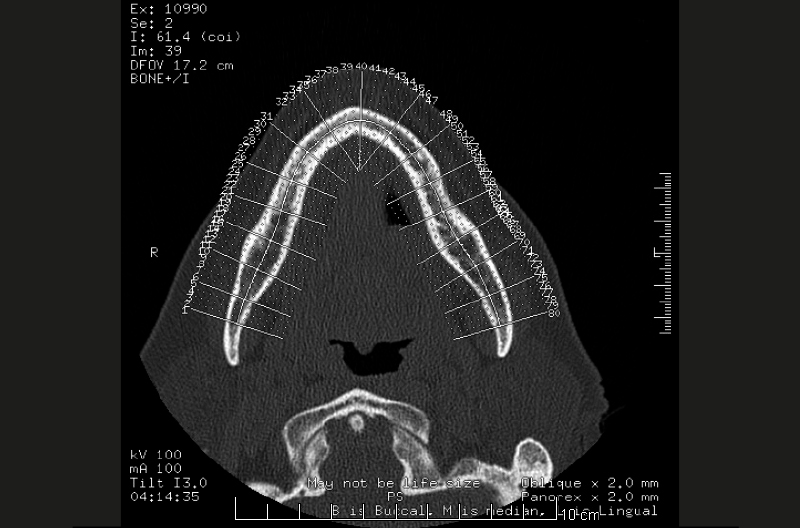

Viste le aspettative della paziente e la quantità di osso disponibile (Fig. 2) si propone come soluzione la tecnica All-on-Four. Il metodo All-on-Four consiste nel posizionare a livello mandibolare quattro impianti intraforaminali, di cui due nella zona degli incisivi laterali e due distali inclinati (“tiltati”) davanti ai forami mentonieri.

- Fig. 2

L’esame Cone Beam ci permette di evidenziare le strutture anatomiche di interesse, i forami mentonieri e il canale incisivo; grazie allo studio dell’esame 3D, vista la disponibilità ossea e la presenza di un osso denso (Figg. 3-6), si decide di utilizzare due impianti Leone diametro 3,3 mm e lunghezza 12 mm e due impianti Leone diametro 3,3 mm e lunghezza 10 mm.